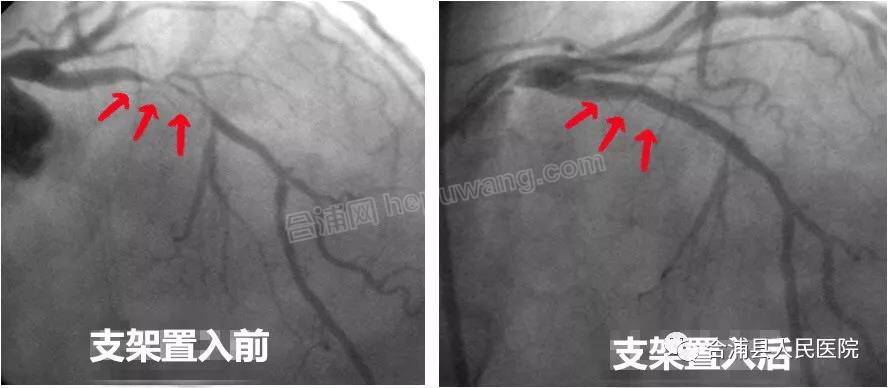

根据目前肝动脉栓塞化疗进展,结合临床经验,对门脉主干瘤栓,巨大肝癌的患者,我院普外二区采用动脉灌注化疗与栓塞化疗结合小量多次栓塞的方法,收到了较好的临床疗效。

肝癌目前虽然是以手术为主的治疗,但综合治疗更为重要,如肝癌术后介入疗法,不仅能发现残存的病灶,而且可以预防术后的复发、转移。肝癌通过介入治疗使肿瘤缩小获得切除的机会。另外,介入治疗结合靶向治疗、生物免疫治疗,能够进一步提高疗效。

合浦人民医院普外二区开展肝肿瘤介入治疗以来,已让众多肝癌中晚期患者受益,为他们带来了新的希望。 胸腰椎椎体压缩性骨折椎体成形术是在DSA引导下,用经皮穿刺的方法,用球囊被压缩的椎体撑开恢复高度后将骨水泥注入,从而达到被压缩椎体高度复原、增强椎体强度和稳定性 、防止塌陷、疼痛部分或完全缓解的目的。它具有创伤小,将穿刺针插入椎体即可;安全性高,无严重并发症;疗效肯定,患者术后即刻或几天内腰背痛症明显减轻或消失,并且疗效可长期维持等优点。